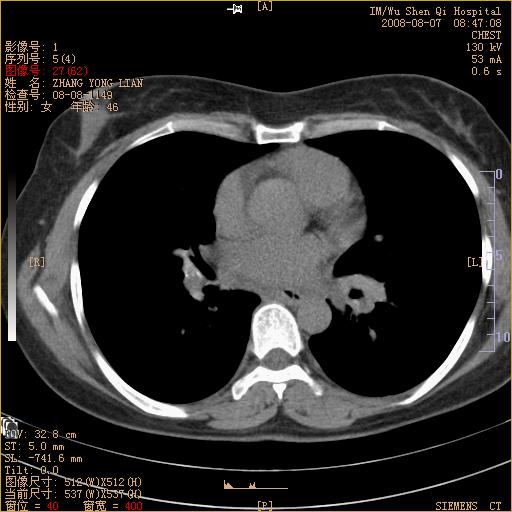

标题: CT15050:女,46岁,咳嗽胸痛一月余 [打印本页]

纵隔窗没发全,左下肺近胸膜处结节。有长毛刺,纵隔淋巴结增大,不排除恶性病变。

考虑肺癌

考虑左肺下叶后基底段周围型肺癌伴纵隔淋巴结转移可能性大。

左下肺ca并纵隔及左肺门区淋巴结转移。

脾脏低密度结节转移不排除。

1)考虑左肺下叶后基底段周围型肺癌伴纵隔淋巴结转移。2)脾内低密度灶,性质待定;不排除转移瘤可能。

恶性度很高的肺癌.